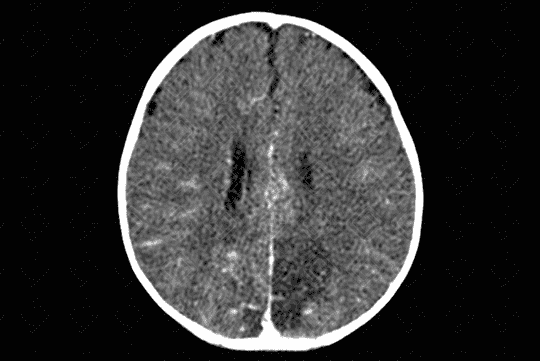

Texto alternativo para a imagem Figura 2. Créditos: Dra. Elazir Mota - Rio de Janeiro/RJ

Descrição da lesão: Acidente vascular encefálico isquêmico (AVE).

Descrição das figuras 1, 2 e 3: Tomografia computadorizada do crânio após a administração do contraste evidenciando extensa hipodensidade nas regiões parietal e occipital esquerdas com extensão ao tálamo deste lado (visualizado na reconstrução sagital), sem causar efeito compressivo, compatível com evento isquêmico subagudo (setas vermelhas).

Por volta de 24 a 72 horas, de fato, surge a hipodensidade do território vascular acometido (figuras 1, 2 e 3).